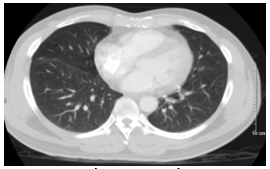

Hình 2: Hình ảnh chọc sinh thiết tổn thương vùng phổi phải dưới hướng dẫn chụp cắt lớp vi tính lồng ngực

Bệnh nhân được chụp PET/CT tại Bệnh viện Vinmec cho kết quả: Các nốt đặc rải rác thùy giữa và dưới phổi phải, các nốt lớn tăng chuyển hoá FDG (suvmax 3,6), ít dịch màng phổi dày 9mm, nhiều nốt rải rác màng phổi thành ngực, hạch nhóm 2R,4R/7 rốn phổi phải, hạch lớn KT 17x10mm.

Hình 3: Hình ảnh chụp PET/CT các nốt tổn thương u tại phổi phải (mũi tên đỏ), nốt di căn màng phổi phải (mũi tên vàng)

Hình 4: Hình ảnh chụp PET/CT: Hạch trung thất, dịch màng phổi phải (mũi tên chỉ)